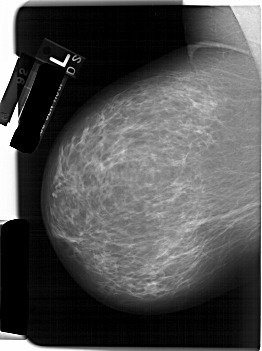

A_1232_1.RIGHT_MLO

A_1232_1.RIGHT_CC

RIGHT_CC LINES 6406 PIXELS_PER_LINE 4456 BITS_PER_PIXEL 12 RESOLUTION 43.5 OVERLAY

RIGHT_MLO LINES 6196 PIXELS_PER_LINE 4336 BITS_PER_PIXEL 12 RESOLUTION 43.5 OVERLAY

FILE: A_1232_1.RIGHT_MLO.OVERLAY

TOTAL_ABNORMALITIES 1

ABNORMALITY 1

LESION_TYPE CALCIFICATION TYPE PLEOMORPHIC DISTRIBUTION LINEAR

ASSESSMENT 4

SUBTLETY 3

PATHOLOGY MALIGNANT

TOTAL_OUTLINES 1